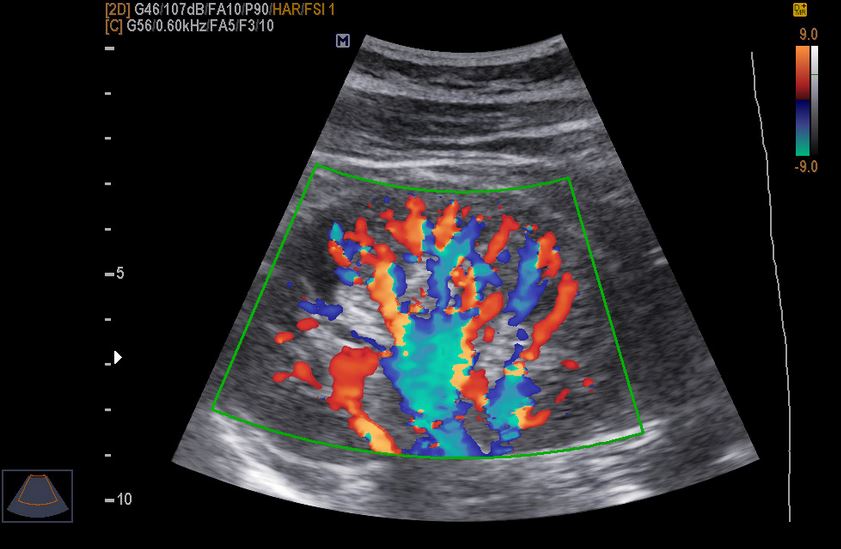

Доплер-эффект основан на том, что ультразвуковые волны, отражаясь от движущихся частиц (при исследовании сосудов – кровяных клеток), меняют свою частоту. Аппарат УЗИ, снабженный специальным каналом, может улавливать эти изменения и преобразовывать их в картинку на мониторе – черно-белый график и очертание сосуда с цветным изображением движущейся крови. Такая методика ультразвуковой диагностики получила название доплерография, если же присутствует цветная картинка – дуплексное сканирование сосудов или цветовое доплеровское кодирование.

Основная задача доплерографии – оценить кровоток в изучаемом сосуде. Чаще всего врачи обследую с помощью УЗИ с доплером магистральные артерии головы и шеи, вены и артерии конечностей, сосуды фетоплацентарного комплекса (матки, плаценты и пуповины у будущих мам), брюшную аорту и ее крупные ветви, почечные артерии и вены, сосуды полового члена и мошонки у мужчин. Помимо этого, доплерографией может дополняться ультразвуковой осмотр любого внутреннего органа (печени, щитовидной железы, матки и т.д.).